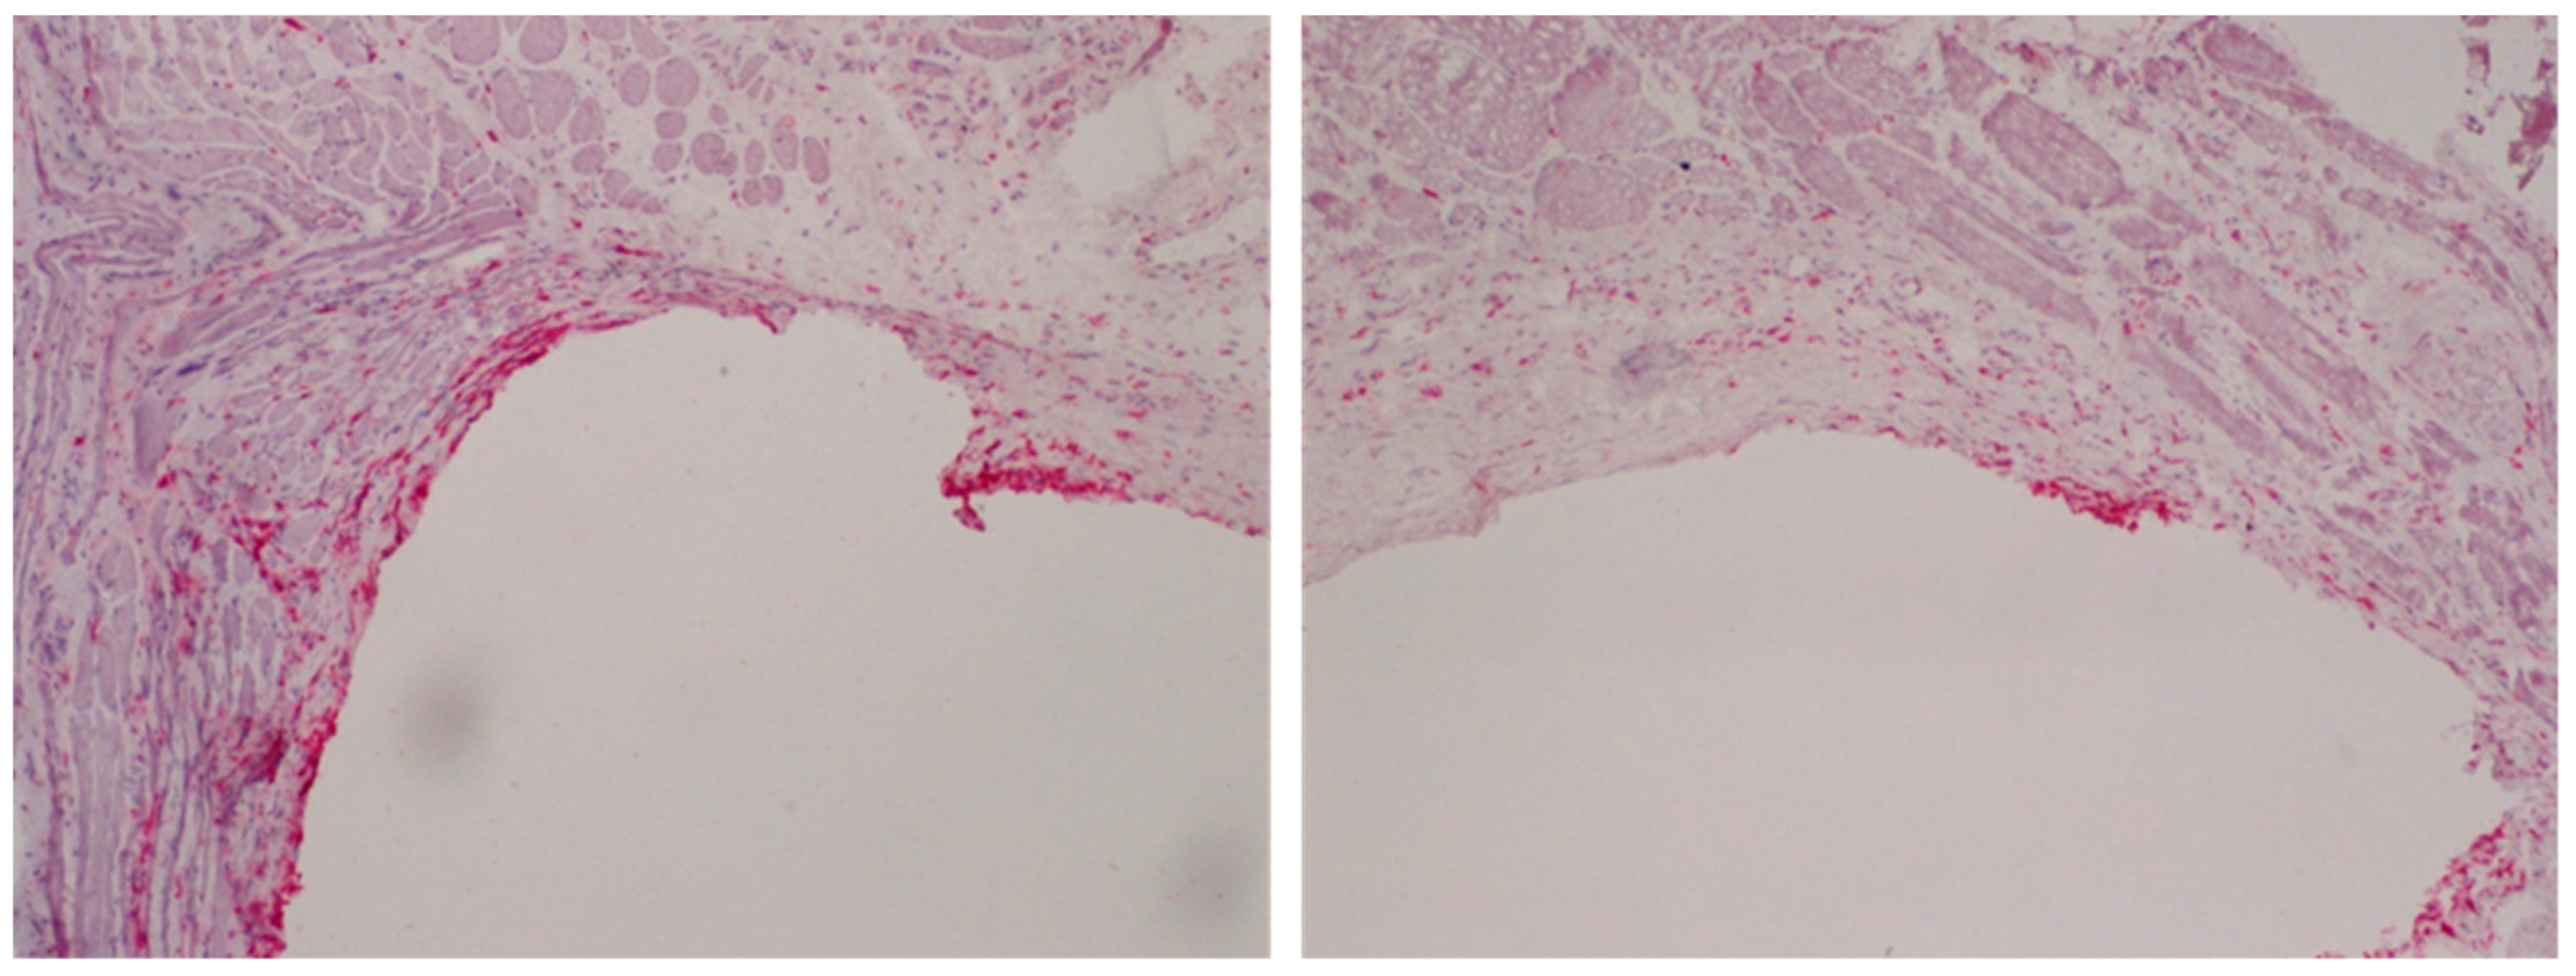

1.3. In Vivo Outcome

- Gabler, C.; Zietz, C.; Göhler, R.; Fritsche, A.; Lindner, T.; Haenle, M.; Finke, B.; Meichsner, J.; Lenz, S.; Frerich, B.; et al. Evaluation of osseointegration of titanium alloyed implants modified by plasma polymerization. Int. J. Mol. Sci. 2014, 15, 2454–2464. [Google Scholar] [CrossRef] [PubMed]

- Hoene, A.; Walschus, U.; Patrzyk, M.; Finke, B.; Lucke, S.; Nebe, B.; Schroeder, K.; Ohl, A.; Schlosser, M. In vivo investigation of the inflammatory response against allylamine plasma polymer coated titanium implants in a rat model. Acta Biomater. 2010, 6, 676–683. [Google Scholar] [CrossRef] [PubMed]

- Walschus, U.; Hoene, A.; Patrzyk, M.; Lucke, S.; Finke, B.; Polak, M.; Lukowski, G.; Bader, R.; Zietz, C.; Podbielski, A.; et al. A cell-adhesive plasma polymerized allylamine coating reduces the in vivo inflammatory response induced by Ti6Al4V plates modified with plasma immersion ion implantation of copper. J. Funct. Biomater. 2017, 8, 30. [Google Scholar] [CrossRef]